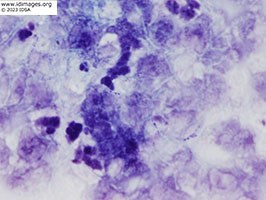

The right calf abscess fluid demonstrated beaded branching gram positive rods on gram stain (Figure 5). Kinyoun stain of leg aspiration demonstrated weakly acid-fast rods (Figure 6). Cultures were notable at 48 hours for chalk white colonies on buffered charcoal yeast abstract (BCYE) (Figure 7) and gram stain revealed branching gram-positive rods. Sanger sequencing of the 16S ribosomal rRNA gene revealed 99% similarity to Nocardia arthritidis. Cell free DNA sequencing of plasma (Karius TestTM) also yielded Nocardia but was unable to distinguish between the following species: Nocardia exalbida, Nocardia gamkensis, Nocardia arthritidis.

- Figure 5: Gram stain of right calf abscess fluid - beaded branching gram positive rods.